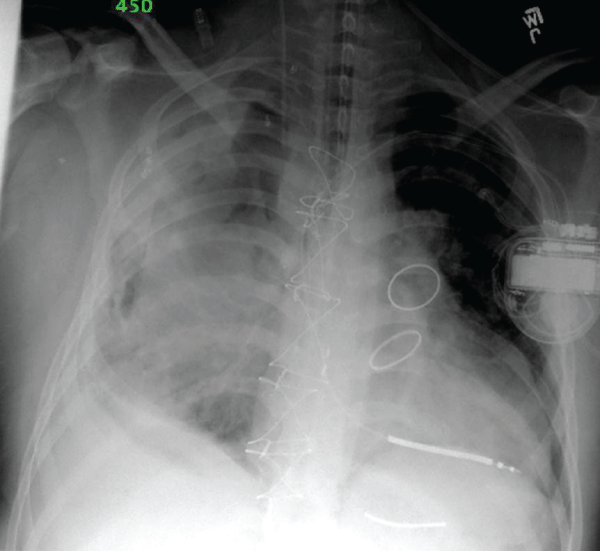

A 22 year old man with a history of truncus arteriosus requiring several surgeries since infancy presented with chest pain and hemoptysis. He had undergone surgery one month prior to repair an aneurysmal graft from a previous aortic valve replacement. Computed tomography showed anterior mediastinal hematoma and right pleural hemothorax. His clinical condition deteriorated, and he required intubation and mechanical ventilation.The predominant source of bleeding was his right lung. Upon cardiac catheterization, all systemic vessels to the right lung were coil embolized. Gas exchange was suboptimal despite the application of escalating peak inspiratory pressures up to 45 cm H2O and mean airway pressures up to 25 cm H2O and 100% oxygen. Results of a representative arterial blood gas were pH 7.19 PaCO2 61 mmHg, PaO2 62 mmHg, and SaO2 87% on 100% oxygen. Extracorporeal Membrane Oxygenation (ECMO) was considered, but contraindicated because of the risks of anticoagulation. Because of the differential requirement of pressure needed to recruit and ventilateeach lung, and the high airway pressure needed to tamponade the right lung, a double lumen endotracheal tube was placed in the left mainstem bronchus for Independent Lung Ventilation (ILV). The occlusive balloon was inflated in the left mainstem to anatomically separate ventilation to the lungs, and each lumen was connected to a separate ventilator. Optimal placement of the side lumen oriented towards the right mainstem was confirmed by bronchoscopy daily. The differential disease is shown in the chest x-ray on the first day of ILV (Figure 1). During the three days of ILV, the less affected left lung was ventilated with conventional mechanical ventilation with a PEEP of 10cm H2O and apeak inspiratory pressure of 35cm H2O to achieve tidal volume of approximately 25 ml. These moderately high settings applied to the less affected lung were required because of the patient's obese body habitus. The right lung was first ventilated with conventional mechanical ventilation with a PEEP of 18 cm H2O and peak inspiratory pressure of 35 cm H2O, initially achieving close to zero tidal volume.Airway pressure release ventilation with a PEEP-high of 25cm H2O and a PEEP-low of 8cm H2O was used subsequently to increase the mean airway pressure for tamponade effect. Fraction of inhaled oxygen to both lungs was 1.0. Adequate gas exchange was achieved with those settings: a representative arterial blood gas from those three days was: pH 7.27, PaCO2 49 mmHg, and PaO2 68 mmHg. After two days of high mean airway pressure, tidal volumes from the right lung increased from zero to 100ml after he was changed back to conventional mechanical ventilation. Modest evidence of recruitment and air Broncho grams are shown on the chest x-ray on the third day of ILV (Figure 2).

Figure 1: Differential disease is demonstrated during the first day of ILV.

There is right-sided pulmonary hemorrhage, and the left lung is relatively

free of airspace disease. The double-lumen endotracheal tube is seen in the

left bronchus. ILV is achieved with the balloon inflated in the left mainstem

bronchus and the “eye” of the proximal lumen oriented towards the right

mainstem bronchus.